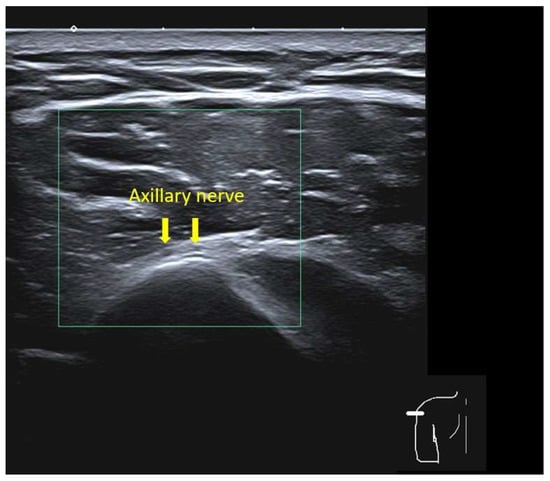

Individualized Deltoid Landmark and Needle Length for Safe Intramuscular Vaccination in Southeast Asian Adults: An Ultrasound Study

Background/Objectives: An incorrect intradeltoid injection technique can cause shoulder injury related to vaccine administration, including bursitis, septic arthritis, and axillary nerve injury, particularly when Western-derived landmarks and needle-length tables are applied to smaller-framed Southeast Asian adults. We aimed to define an individualized deltoid injection landmark and needle length that avoid the axillary nerve while ensuring reliable intramuscular delivery in Southeast Asian adults. Methods: In this cross-sectional ultrasound study of adults aged ≥18 years, four vertical landmarks below the acromion (individual contralateral 2-fingerbreadth (FB), individual contralateral 3-FB, average 2-FB, average 3-FB) were assessed in two arm positions (adduction and approximately 30° abduction with the hand on the waist). For each combination, we recorded the presence of the axillary nerve and measured skin-to-subcutaneous and deltoid muscle thickness to estimate whether 0.5-, 1-, or 1.5-inch needles would terminate within muscle or penetrate the subdeltoid bursa. Results: Eighty-two participants (39 males, 43 females) were included. The axillary nerve was not visualized at the individualized contralateral 2-FB landmark in adduction but was present at 31.7–50.0% of other landmark–position combinations. At the individualized 2-FB site in adduction, mean skin-to-subcutaneous thickness was <12.7 mm and mean skin-to-subdeltoid fascia distance exceeded 12.7 mm in all strata, implying that a 0.5-inch needle would consistently terminate within the deltoid muscle. Conclusions: In Southeast Asian adults, the contralateral individualized 2-FB landmark in arm adduction provides a neurovascularly safe window for intradeltoid vaccination, and a 0.5-inch needle offers reliable intramuscular delivery while minimizing the risk of bursal penetration. Full article

Figure 1